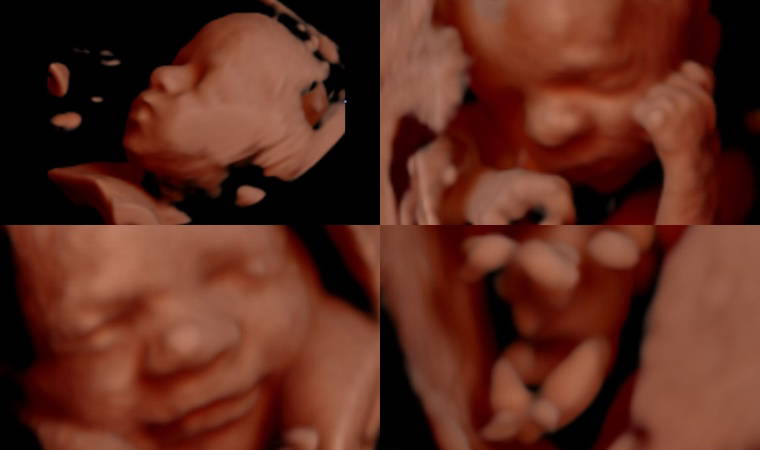

Genelde üç boyutlu ultrason veya renkli ultrason ile karıştırılabilen ayrıntılı ultrason, anne karnındaki bebeğin dört boyutlu görüntüsünün alınmasını sağlar. Ancak dört boyutlu görüntüdeki amaç; bebeğin al, ayak ve yüzünün anne babaya göstermek değil, bebeğin gelişiminde bir anormallik olup olmadığının takibini yapmaktır.